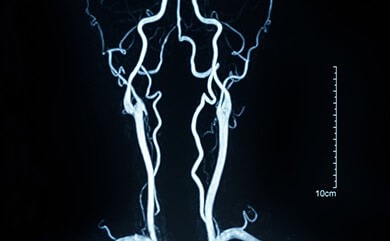

Ангиография и коронарография – диагностика мальформации кровеносных сосудов, тромбозов, обструкций желчных и печёночных протоков, болезней сосудов, закупорка печеночных артерий. Для проверки используется контрастное вещество.

КТ (Компьютерная томография), КТ-ангиография (компьютерная томография сосудов), КТ сердца (Cardioscan). – это метод, сочетающий в себе рентгеновские снимки в различных проекциях, позволяющий получить сверхточное изображение исследуемого органа в трехмерном виде.